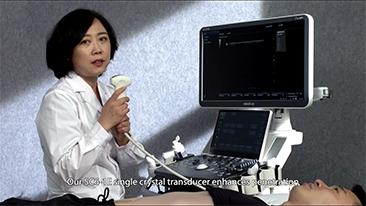

As solu??es de imagem geral Mindray Resona ajudam mĂŠdicos a obter resultados mais precisos e eficientes de diagnĂłstico e tratamento por meio de sondas de aplica??o de subdivis?es abrangentes e ferramentas eficientes de aplica??o clĂnica.

O ambiente mĂŠdico atual se tornou mais complexo, com um nĂşmero crescente de casos difĂceis e cargas de trabalho.